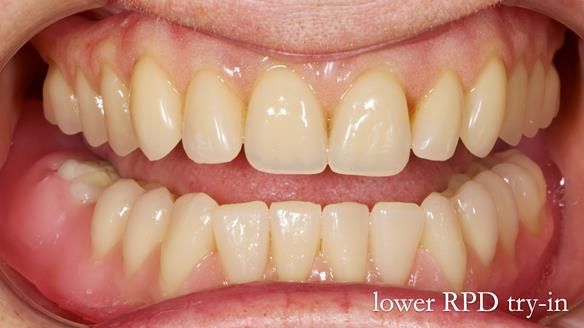

Mary’s upper occlusal plane wasn’t parallel to her interpupillary line, and she specifically wanted that natural asymmetry preserved. Rowan arranged the teeth beautifully, following the exact contour and character of her original smile.

For both the upper and lower dentures, we used Schottlander Enigma Life teeth. I’ve been using these since 2014 and they’ve been outstanding - the surface texture, colour depth, and light reflection are superb. When arranged to mirror the patient’s natural tooth positions, they look completely lifelike.